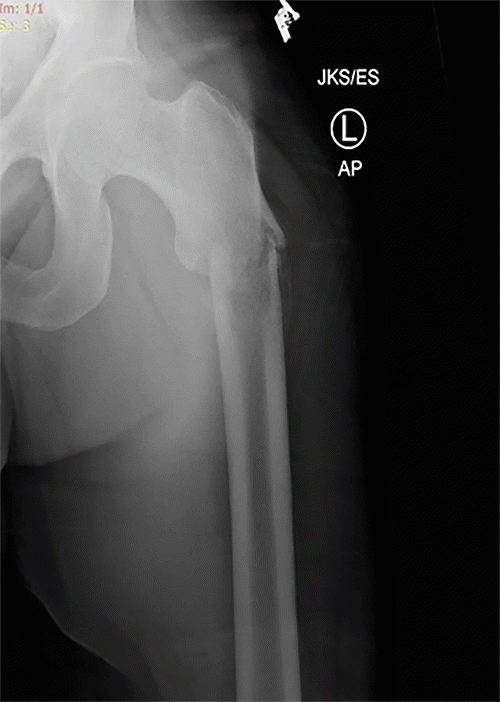

While an urgent oncologic colorectal resection was planned, definitive orthopedic intervention for the stable pathological fracture was initially postponed. This decision was influenced by the patient’s preference to be treated by a specific orthopedic surgeon unavailable at our institution and the near-obstructing nature of the colonic tumor, which prioritized the colorectal surgery. The patient underwent an oncologic laparoscopic low anterior resection under general anesthesia, performed by a board-certified colorectal surgeon assisted by a PGY-5 resident. The perioperative, intraoperative, and immediate postoperative course was unremarkable. Due to his underlying congestive heart failure, he was transferred to the intensive care unit for close cardiac monitoring postoperatively and was subsequently moved to the surgical ward on postoperative day (POD) 3. On POD 4, while ambulating in his room, the patient reported hearing a “cracking sound” and experienced a fall. A spontaneous, closed, displaced left femoral shaft fracture with associated skin tenting was diagnosed. Orthopedic surgery was consulted immediately; the fracture was reduced, and a Buck’s traction device was applied (Figure 2). This unexpected event prompted further surgical intervention, consisting of intramedullary nailing of the femur, during which a bone biopsy was obtained. Histopathological examination of this biopsy unequivocally confirmed metastatic colorectal adenocarcinoma as the underlying cause of the pathological fracture.

Figure 2. Post-Reduction Radiographs of Left Femur with Buck’s Traction. Published with Permission

(A) Anteroposterior and (B) Lateral radiographs of the left femur obtained after closed reduction of a spontaneous pathological shaft fracture. The images demonstrate alignment of the fracture fragments with a Buck's traction device in place